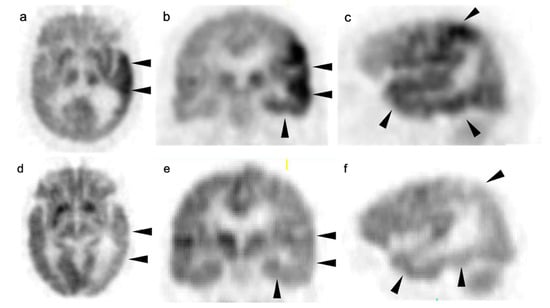

3.2. Paraneoplastic CNS Manifestations and Sources of False Positive FDG PET Scans That Can Mimic Brain Tumors

3.3. Primary Brain Tumors